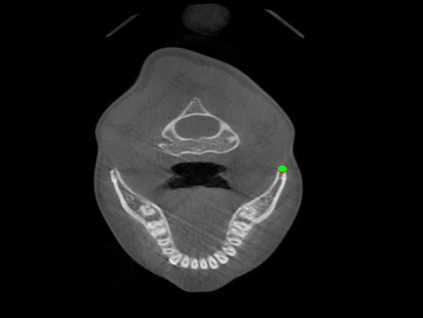

Detecting 3D landmarks on cone-beam computed tomography (CBCT) is crucial to assessing and quantifying the anatomical abnormalities in 3D cephalometric analysis. However, the current methods are time-consuming and suffer from large biases in landmark localization, leading to unreliable diagnosis results. In this work, we propose a novel Structure-Aware Long Short-Term Memory framework (SA-LSTM) for efficient and accurate 3D landmark detection. To reduce the computational burden, SA-LSTM is designed in two stages. It first locates the coarse landmarks via heatmap regression on a down-sampled CBCT volume and then progressively refines landmarks by attentive offset regression using multi-resolution cropped patches. To boost accuracy, SA-LSTM captures global-local dependence among the cropping patches via self-attention. Specifically, a novel graph attention module implicitly encodes the landmark's global structure to rationalize the predicted position. Moreover, a novel attention-gated module recursively filters irrelevant local features and maintains high-confident local predictions for aggregating the final result. Experiments conducted on an in-house dataset and a public dataset show that our method outperforms state-of-the-art methods, achieving 1.64 mm and 2.37 mm average errors, respectively. Furthermore, our method is very efficient, taking only 0.5 seconds for inferring the whole CBCT volume of resolution 768$\times$768$\times$576.